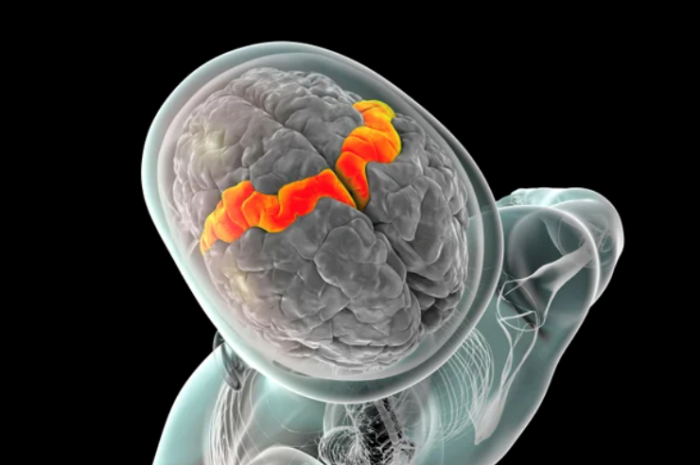

Não của những người khỏe mạnh lão hóa nhanh hơn trong đại dịch Covid-19

Các nghiên cứu trước đây từng gợi ý rằng nhiễm SARS-CoV-2 có thể làm trầm trọng thêm tình trạng thoái hóa thần kinh và suy giảm nhận thức ở người lớn tuổi. Nhưng ít nghiên cứu xem xét liệu giai đoạn đại dịch – khoảng thời gian đầy xáo trộn đối với nhiều người do các đợt giãn cách và phong tỏa buộc họ phải thay đổi lối sống và bị căng thẳng – có tác động đến lão hóa não hay không, theo đồng tác giả Ali-Reza Mohammadi-Nejad, nhà nghiên cứu hình ảnh thần kinh tại Đại học Nottingham (Vương quốc Anh).